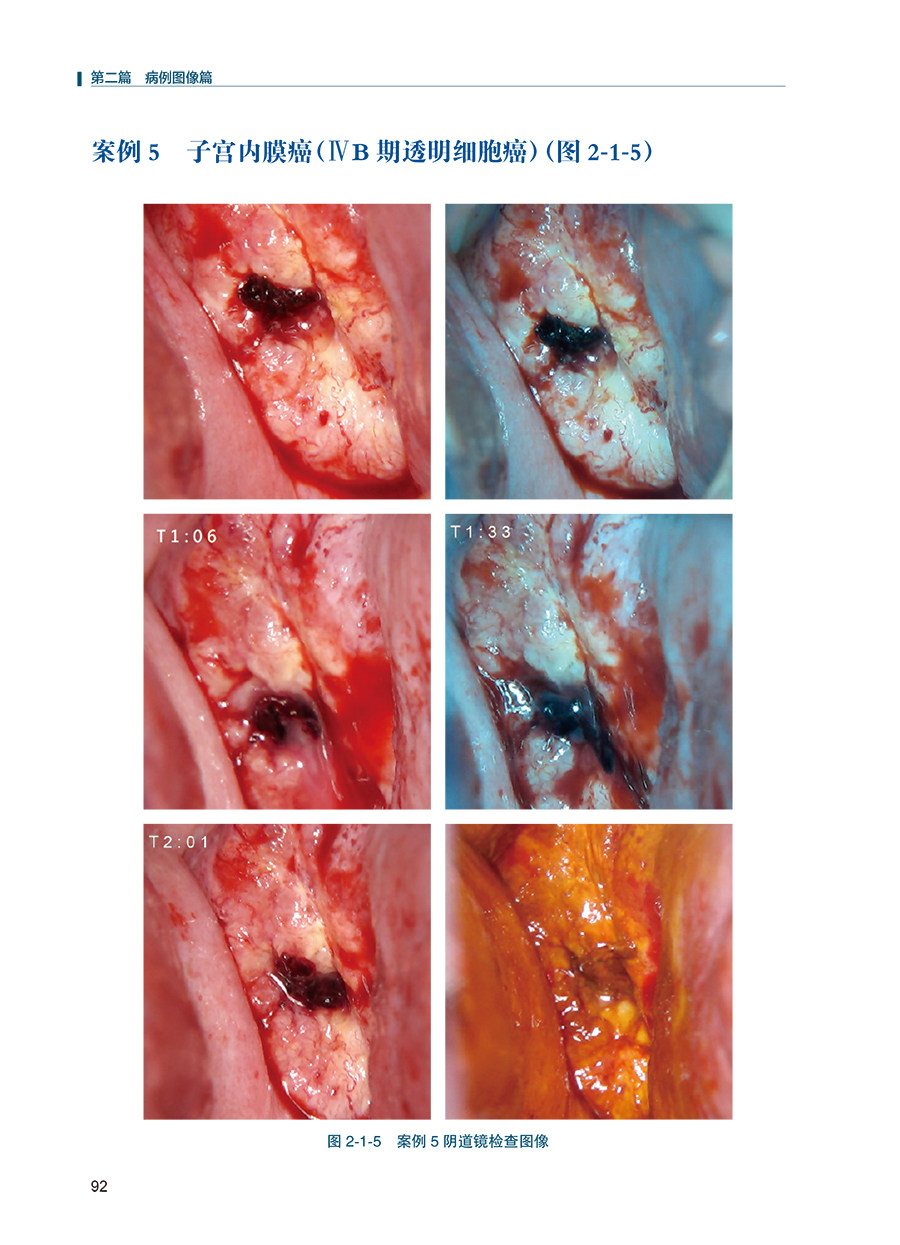

本书系统地对R-way阴道镜诊断路径做了详细的介绍,包括宫颈病变的病理组织学基础、R-way阴道镜诊断路径术语、操作方法和鉴别诊断。主要内容包括阴道镜下宫颈癌、高级别病变、低级别病变及正常阴道镜所见共100例病例,其中每一例均包括宫颈脱落细胞学、人乳头瘤病毒检测、阴道镜图谱及组织病理学结果。另附加作者对案例诊断路径的解读。诊断流程图文并茂、思路清晰,各种诊断信息完善,最终提供组织病理学结果。读者学习后相当于自己完成100例阴道镜检查诊断,对今后的阴道镜的诊断水平将有大幅度提升。